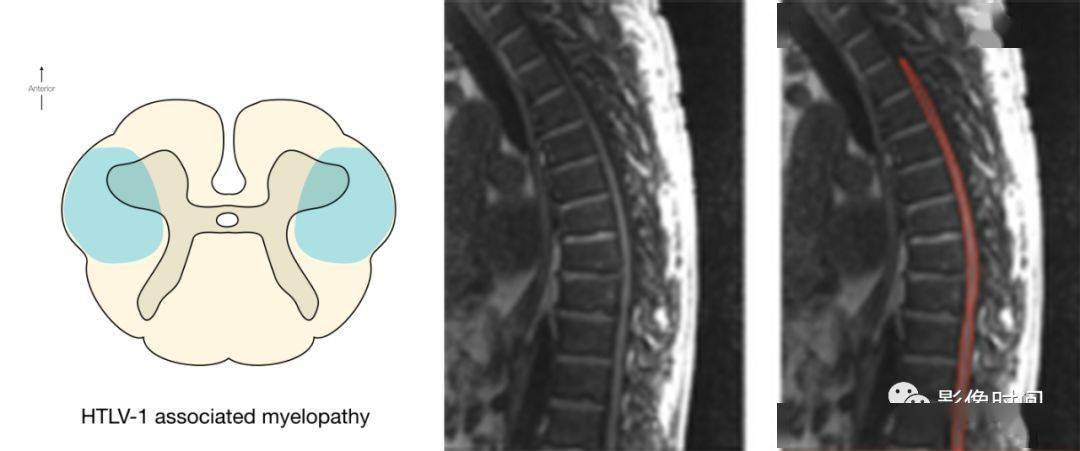

17 种脊髓病变影像解读,你 get 了吗

图片尺寸1080x451